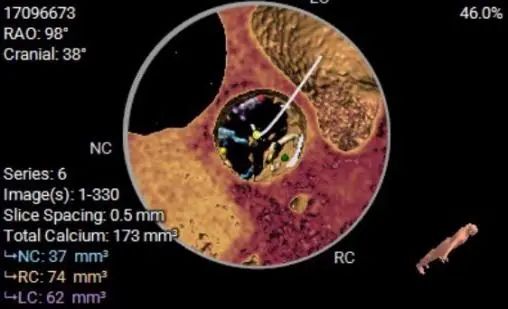

钙化分布:HU850:852.2m³

手术策略与讨论

Typ1型二叶瓣,极重度钙化,瓣膜锚定力可,预估瓣膜形态影响较大,钙化分布于瓣叶上,结 合流出道形态及瓣上多平面分析,预估瓣膜释放后下滑风险较高,少量偏多瓣周漏可能。

左右冠开口高度可,综合瓦氏窦内径、窦管交界内径等因素考虑,冠脉风险较低 。

计划使用22mm球囊进行有扩张,瓣膜进行释放,结合流出道形态及瓣上多平面分析,26瓣膜进行释放,结合流出道形态及瓣上多平面分析,采取释放高度瓣膜下3mm左右。